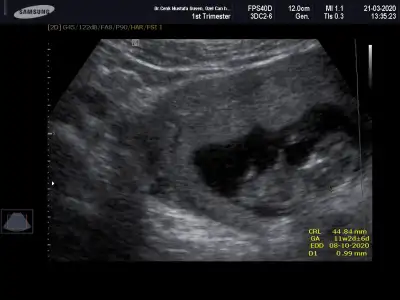

Merhaba yeni uyeyim elimde 7 haftalik karindan 10 haftalik alltan ulturason goruntusu var cinsiyet tahmini yapabilirmisiniz acaba şimdiden teşekkurler ilk resim 7 hafta karin son resim 10 haftta altan bakildi.

Keseye göre erkek ama tutmayabilir siz 11 12 13 haftaları paylaşın